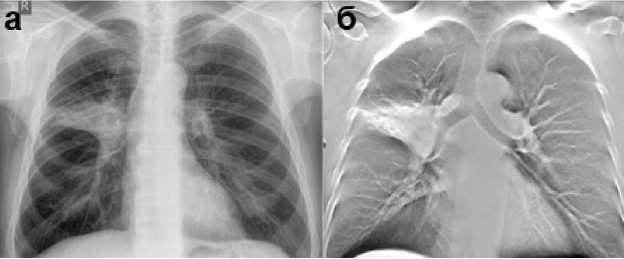

На рентгенограмме определяется ателектаз С3 правого лёгкого, тогда как на ТС хорошо видна ампутация В3.

Заключение: Рак верхней доли правого лёгкого.